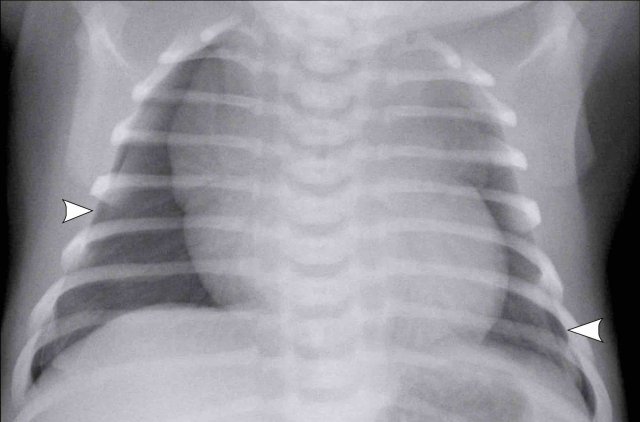

Image

Full term infant shortly after birth with mild pulmonary distress.

• Mild diffuse linear opacification of both lungs in keeping with TTN.

• Bilateral pneumothorax (arrowheads).

• Sharpening of the mediastinal structures on both sides as a result of interface between mediastinum and pneumothorax.

Due to fluid in the lung parenchyma these lungs were stiff and did not collapse.